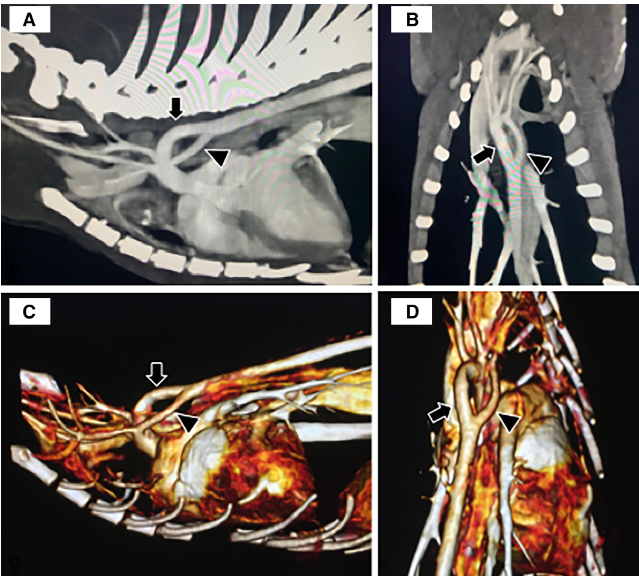

개와 고양이의 이중대동맥궁

개에서는 동맥관개존증이 가장 일반적인 심혈관계 선천 질환이지만 사람에서는 이중대동맥궁이 더 많다고 한다.

하지만 소형동물에서는 이중대동맥궁이 드물어 현재까지 보고된것도 개와 고양이 모두 해서 12마리만 보고되어 있는 정도이다.

증상은 PRAA 등과 같이 섭식 장애를 유발하는것이 일반적이고

수술은 혈관 한쪽을 결찰후 절단하는 방법인데 이에 대한 예후 평가에 대한 논문이다.

결론은 수술을 했더니 장기적으로 삶의 질이 늘어나더라. 라는것.